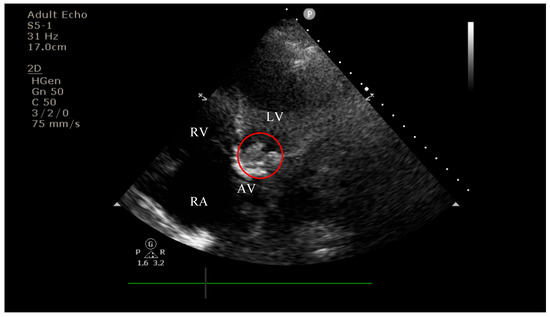

4.2. Diagnostic Findings: Mitral Valve Dysfunction and Embolic Phenomena